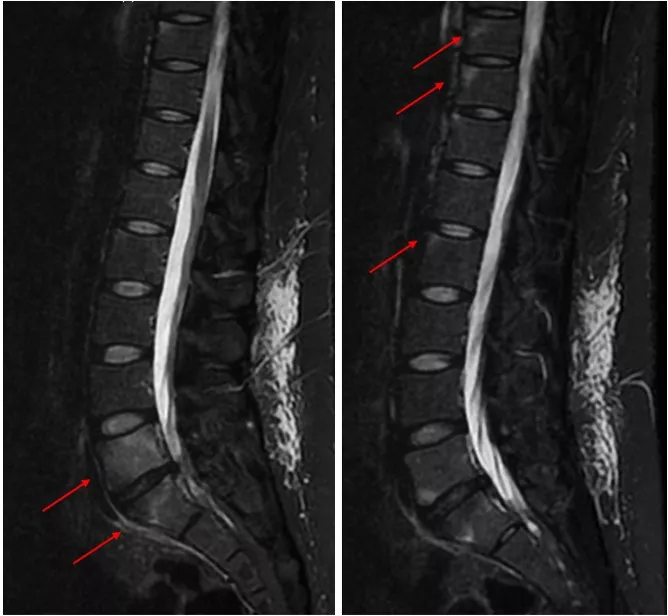

なお全身CTでは胸鎖関節や胸肋関節に骨化像なし。しかし仙腸関節MRI脂肪抑制画像では活動性炎症所見は明らかでなかった(写真4)。

典型的な炎症性背部痛の病歴を有していたこと、MRIで仙腸関節に活動性炎症所見はないがCTで以前の炎症を示唆する所見が示唆されたことなどから、総合的にX線基準を満たさない体軸性脊椎関節炎と診断した。NSAIDs内服は無効であったため、生物学的製剤による治療を開始した。

写真4 仙腸関節MRI